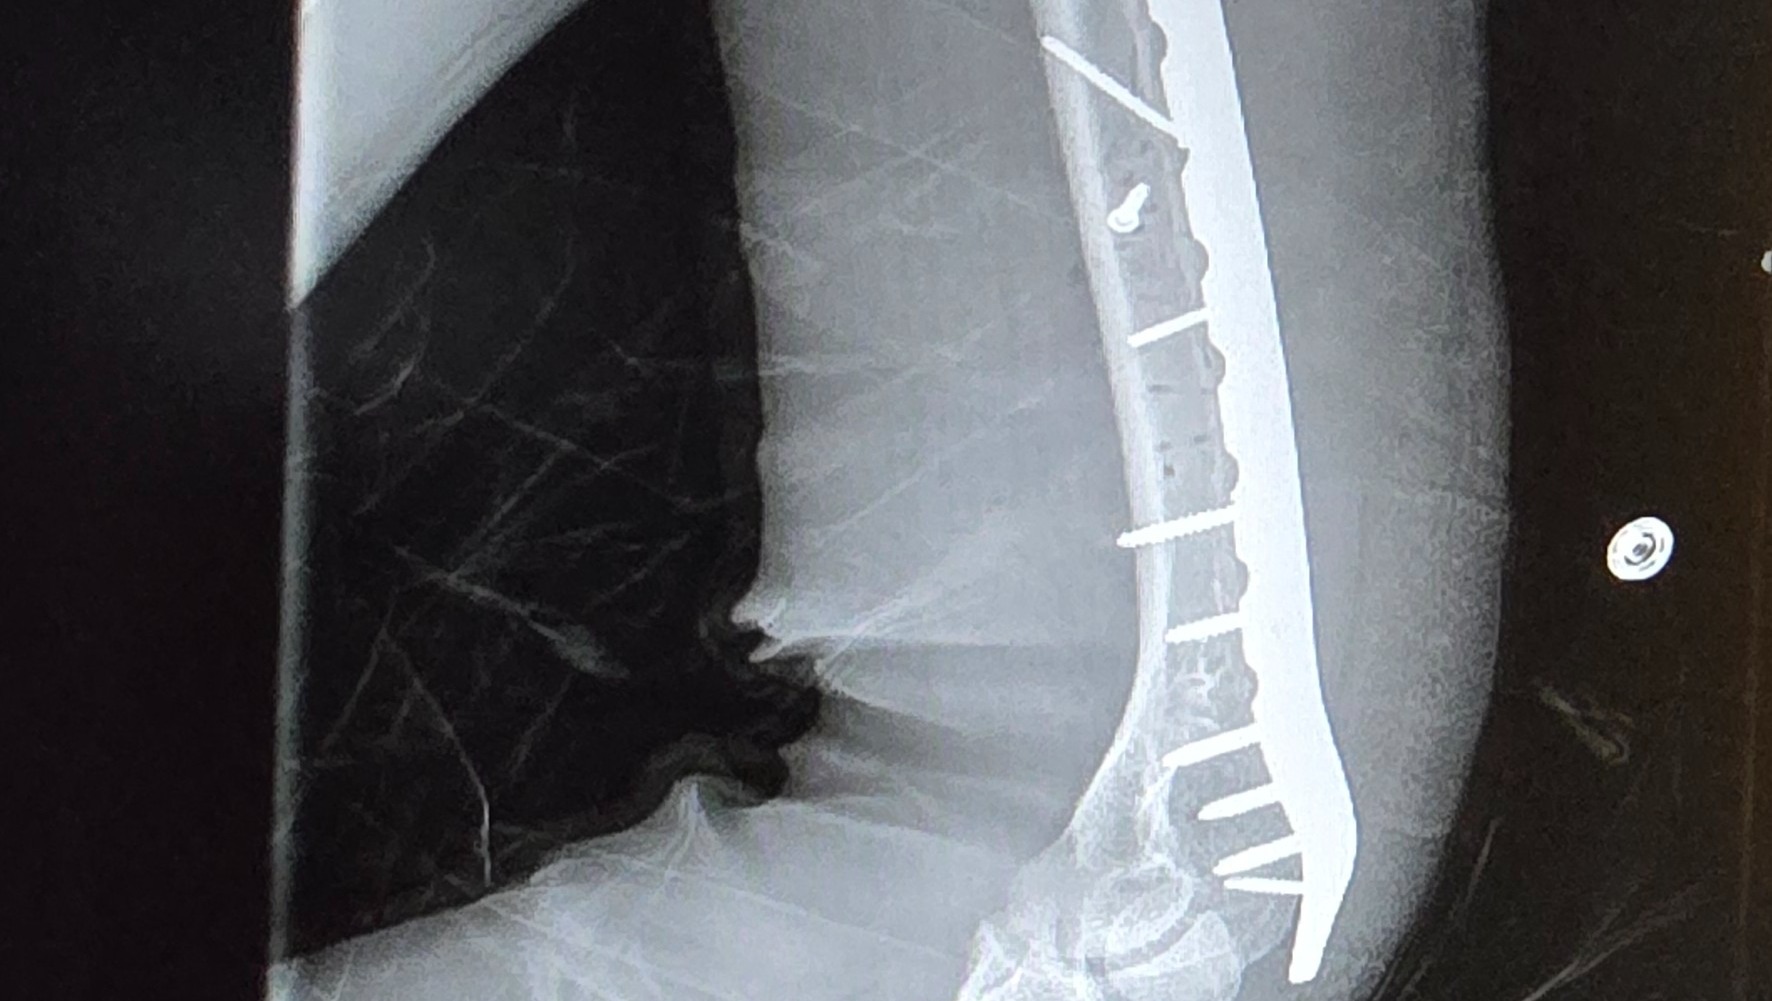

Even though he was wearing his seatbelt, the entire impact hit his left side. His left arm was shattered into multiple pieces, causing severe nerve damage. His left femur was broken into three pieces. He also struck his head against the window.

He was rushed to the hospital, where he spent a long night in unbearable pain before undergoing nearly eight hours of emergency surgery the next morning. Surgeons worked tirelessly to reconstruct his arm and leg. Today, Cole lives with metal rods and screws permanently placed in both his arm and leg.